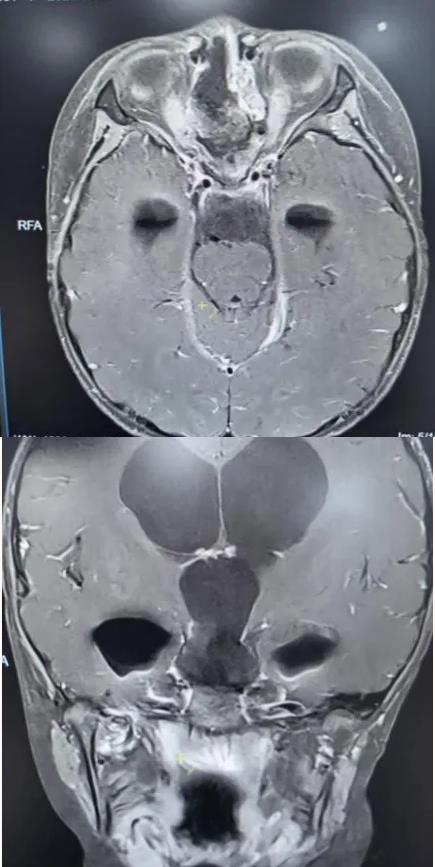

术后垂体MRI增强检查

手术中,团队借助高清4K神经内镜,凭借精湛的显微操作技术,细致分离肿瘤与周围神经、血管的粘连。历经3小时,肿瘤被完整切除,下丘脑、垂体柄、视神经等重要结构均得到完好保护。术后病理确诊为颅咽管瘤。

在医护团队的精心照护下,欢欢神经功能障碍明显改善,视力逐渐恢复,头痛症状完全消失,梗阻性脑积水得到有效缓解。之后顺利拔除脑室引流管,未出现脑脊液漏、感染等并发症,内分泌功能也通过药物获得精准调控。